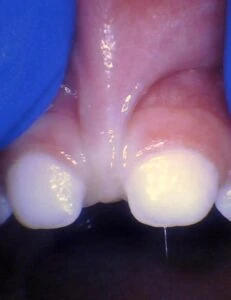

IMAGES OF TONGUE- AND LIP-TIES

Posterior tongue-tie in an infant seen with lifting the tongue. The posterior or “hidden”tongue-tie can cause the same symptoms including nursing pain and poor weight gain, as a to-the-tip tie in an infant